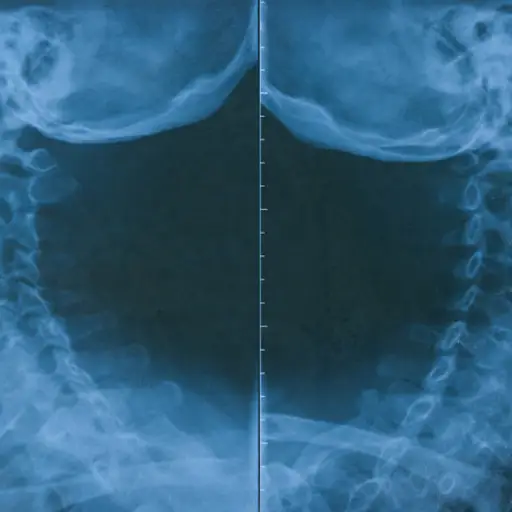

X射线表明,我的类风湿性关节炎(RA)可以制作将我的脊椎连接到我的头骨不稳定的关节。这真的是你想要不稳定的最后一个地方:损坏可能导致严重的脊髓损伤或更糟。幸运的是,CT扫描透露,我没有危险,但在我的研究中,我了解到10人中有8人,Ra有一些颈部问题。他们并非所有人都危及生命,但它们是我们需要了解的问题。

当类风湿性关节炎影响关节时,它会导致骨骼侵蚀和韧带松弛。在颈部,这可能会导致第一和第二椎体(寰枢关节)之间的不稳定,当你头向前或向后倾斜时,也会出现排列问题。德克萨斯州里士满纪念赫尔曼·凯蒂医院(Memorial Hermann Katy Hospital)的风湿病学家、医学博士拉贾特·巴特(Rajat Bhatt)说,如果病情恶化,神经可能会受到冲击,导致四肢无力和麻木。严重的不稳定还可能导致脊髓受压,这可能是致命的。幸运的是,关节融合术可以消除这种风险(稍后会详细介绍)。